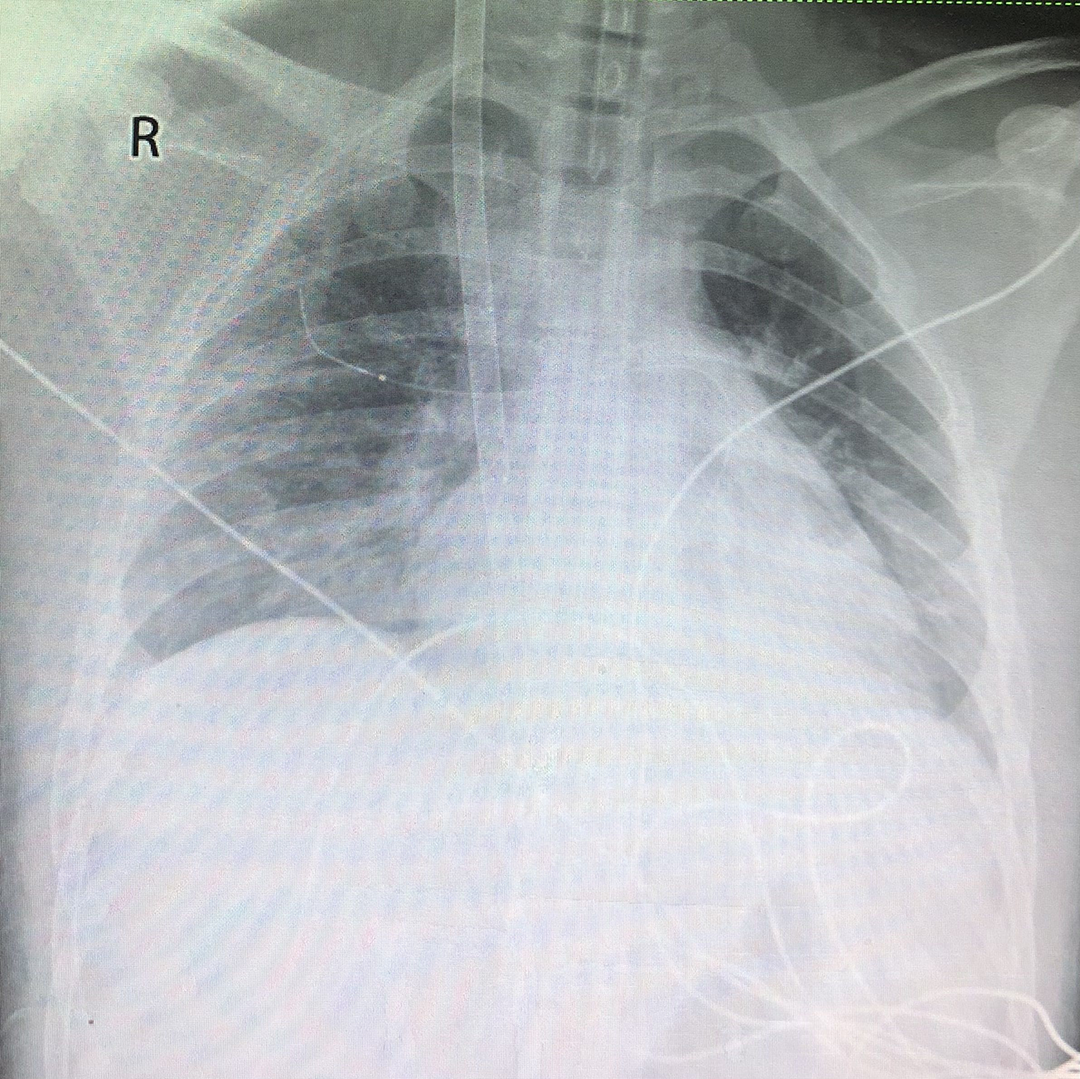

X线显示导管置入位置准确良好

Crescent不透射线标记:“X射线下的置管及日常定位”成为可能

为了精准管道定位,此次操作由北京大学深圳医院任明明教授团队在DSA引导下进行精准双腔ECMO插管置管定位。此次应用的Crescent双腔颈静脉插管,因独家设计的不透射线标记,可在X线下清晰辨识,为插管的置管(及后续日常定位)提供了极大便利。